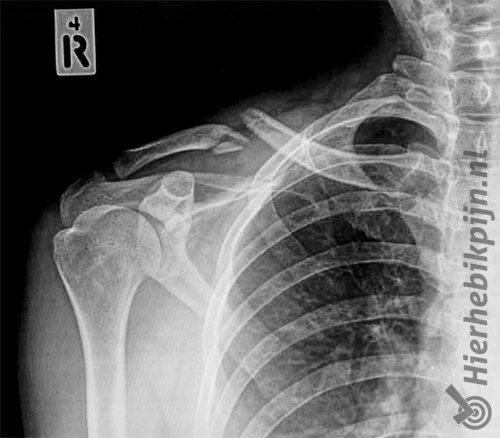

Foto Clavicula fractuur / sleutelbeenbreukFoto Clavicula fractuur / sleutelbeenbreukFoto Clavicula fractuur / sleutelbeenbreuk

Een sleutelbeenfractuur is niet moeilijk te diagnosticeren omdat het sleutelbeen erg oppervlakkig ligt. Hierdoor is een breuk eenvoudig te zien en te voelen. Een röntgefoto wordt meestal gemaakt om een indicatie te krijgen van de breuk en de stand van het sleutelbeen. Dit geeft inzicht in het herstelproces en kan problemen met onderliggende weefsels zoals zenuwen en bloedvaten uitsluiten.

Als na een röntgen foto blijkt dat de fractuur een te grote verplaatsing van het sleutelbeen geeft, of dat de breuk een onstabiele fractuur is, dan wordt een operatie overwogen.